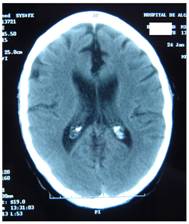

Figure 4 represents and example of ischemic stroke and hemorrhagic stroke on baseline and delayed CT with edema developing after 48 hours.

FIGURE 5

A. CT on admission. Hemorrhagic stroke presenting with headache and left hemiplegia. CRP level: 3.23 mg/dL. NT-PBNP level: 66.3 pmol/L. B. CT scan after 48 hours in the same patient. See the surrounding hypoatenuation of the hematoma with increased mass-effect. CRP level: 22.6. NT-PBNP level: 197 pmol/L.